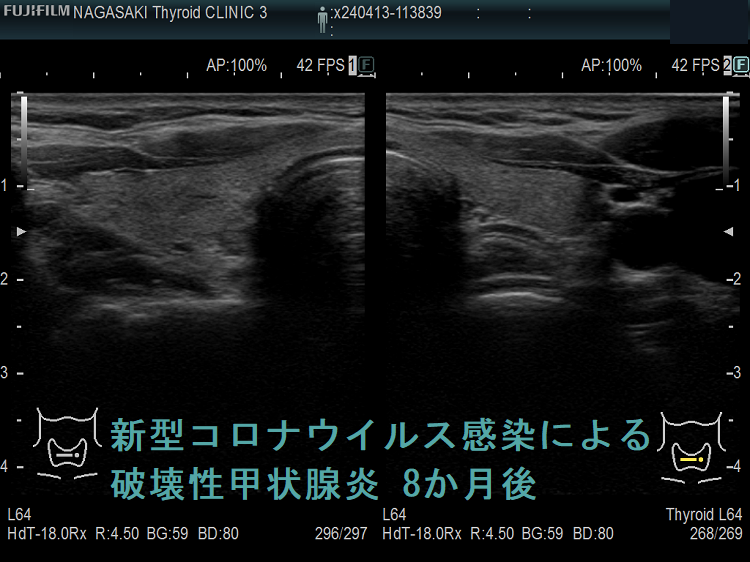

下の写真は、新型コロナウイルス肺炎に罹った甲状腺機能正常橋本病患者の感染前後計12か月の超音波(エコー)画像です。新型コロナウイルス肺炎になる6か月前と6カ月後に、1年に1回の定期検査で長崎甲状腺クリニック(大阪)を訪れていました。新型コロナウイルス肺炎発症時の甲状腺機能は不明ですが、少なくとも6カ月後は正常でした。しかし、発症前に比べて甲状腺は腫大し、腹側(写真下部)の低エコー領域(黒い部分)が拡大しており、橋本病の炎症が増悪したと推察されます。新型コロナウイルス肺炎発症時には破壊性甲状腺炎(無痛性甲状腺炎)を起こしていても不思議ではありません。

以下は、長崎甲状腺クリニック(大阪)の自験例です。

長崎甲状腺クリニック(大阪)の自験例

急性期

1.5か月後

5か月後